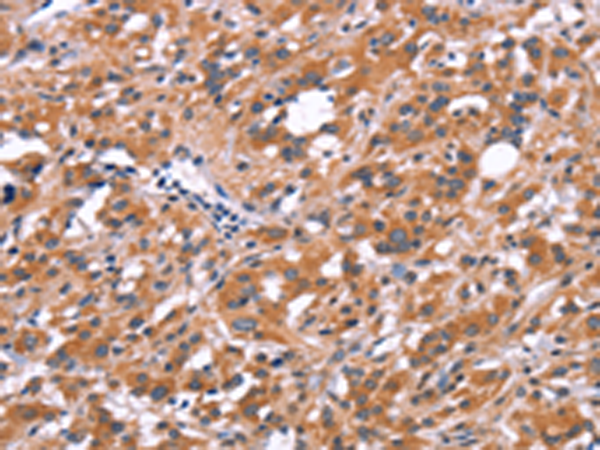

分类: 科研抗体货号: P04914别名: H963应用: WB,IHC反应种属: Human